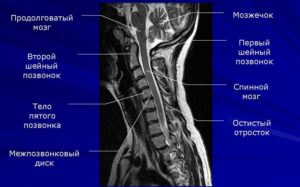

Шейный отдел располагается в верхней части позвоночного столба и состоит из позвонков. Он имеет легкий изгиб в виде буквы «С», при этом выпуклая сторона обращена вперед. Это физиологическое состояние.

Шейный отдел позвоночника является самым мобильным. Подвижность помогает выполнять движения головой в стороны, делать повороты и наклоны. Поперечные артерии располагаются в отростках шейных позвонков. Они принимают участие в кровоснабжении мозга, мозжечка. Сдавливание позвоночной артерии происходит в результате образования грыж или нестабильности в данном отделе.

МРТ шейного отдела позвоночника показывает следующие анатомические структуры:

Магнитно-резонансная томография является единственным методом, позволяющим увидеть патологические и структурные изменения в шейных позвонках, а также оценить патофизиологические и физико-химические процессы в шейном отделе позвоночного столба. МРТ шейного отдела показывает в трехмерном изображении нервные стволы и сосудистую сеть позвоночника.